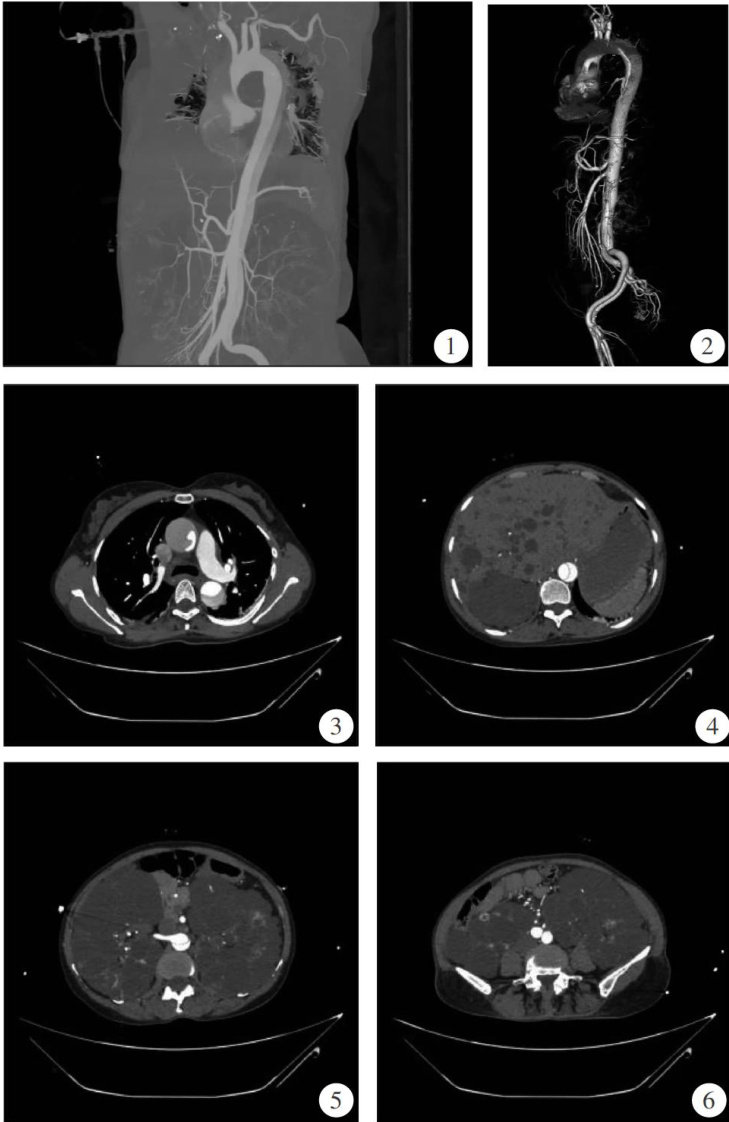

患者女,50岁,于2023年11月19日因“头晕、胸背部闷胀、气短 5h ”入院。患者于当日清晨打扫卫生时突发胸背部闷胀感,伴气短,伴头晕,伴视物模糊,伴双上肢麻木、双下肢酸胀,伴小便失禁于9点左右就诊。患者既往高血压病史10余年,最高达200/100mmHg(1mmHg=0.133kPa) ,规律口服“苯磺酸氨氯地平 ⋅+ 厄贝沙坦片"治疗。(剩余2305字)

主动脉夹层合并多囊肾多囊肝1例